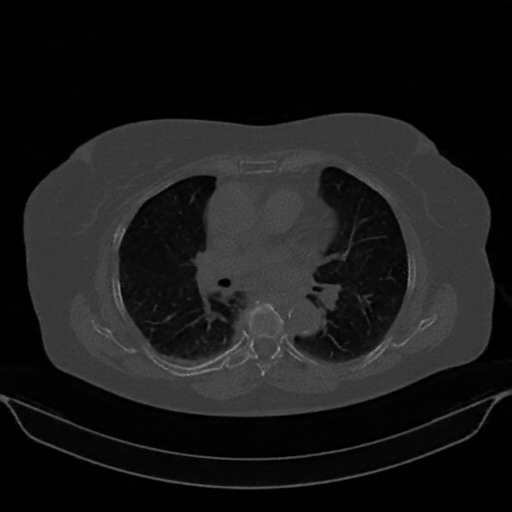

Reconstructed NATIVE CT scan (cycle consistency)

No window - Raw intensity values

Lung window (WL -600, WW 1500 β†’ Low βˆ’1350, High +150)

Mediastinum window (WL 40, WW 400 β†’ Low βˆ’160, High +240)